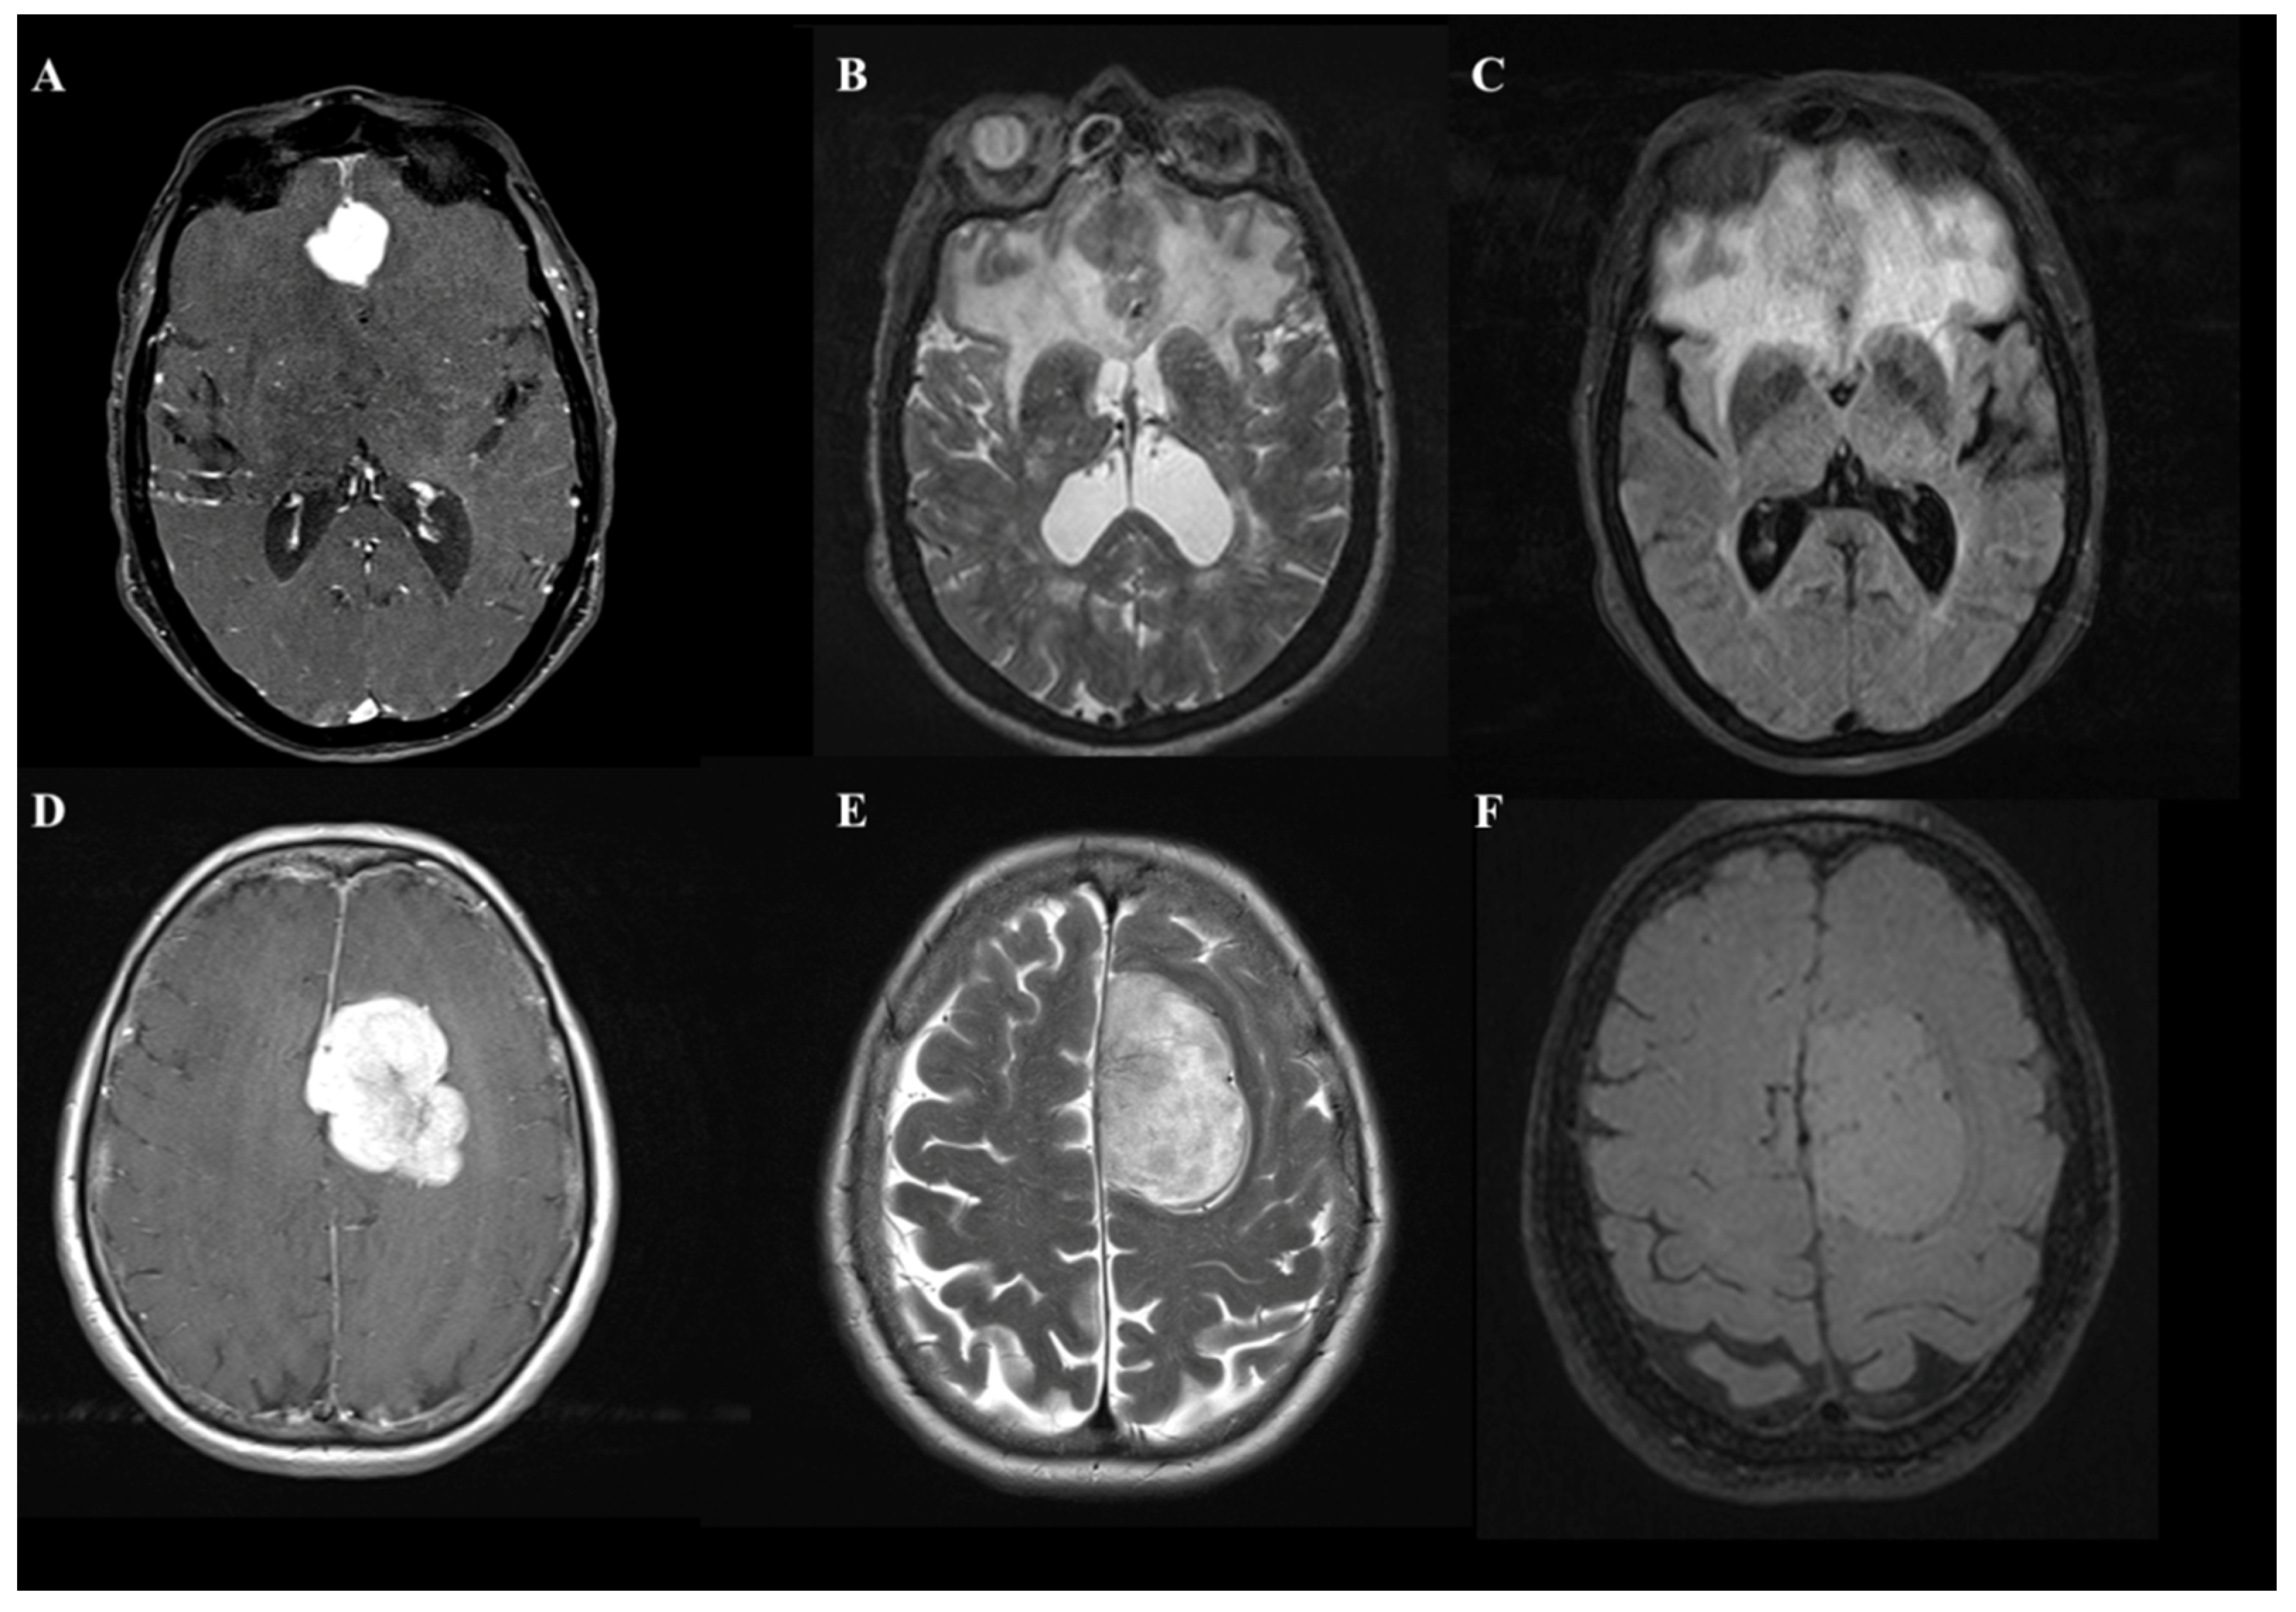

Meningiomas are benign neoplasms arising from meningoendothelial cells [1]. They are the most frequent intracranial tumor in the adult population. Although intracranial meningiomas (IM) are typical extra-axial tumors, the occurrence of peritumoral brain edemas (PBE) are not rare, affecting between 38% to 67% of IM patients [1,2,3]. It is well recognized that a large proportion of PBE can increase morbidity and mortality [2] and determine brain displacement, increase intracranial pressure [3], and add the risk of perioperative seizures [4]. In daily clinical practice, it is not uncommon for a neurosurgeon to confront the diagnosis of an IM with a large proportion of edema irrespective of the site and size of the contrast-enhancing lesion (Figure 1).

Figure 1. A comparison of two cases of patients with frontal lobe meningioma with an asymptomatic onset that, on MRI images, document entirely different volumes of edema. In the first case, T1-weighted with MDC (A), T2-weighted (B), and FLAIR (C) images show a 2 cm para-alpine lesion with edema involving the entire frontal lobe. In the second case, the identical sequences (DF) show a more than 4.5 cm lesion in diameter with a volume of edema almost absent.